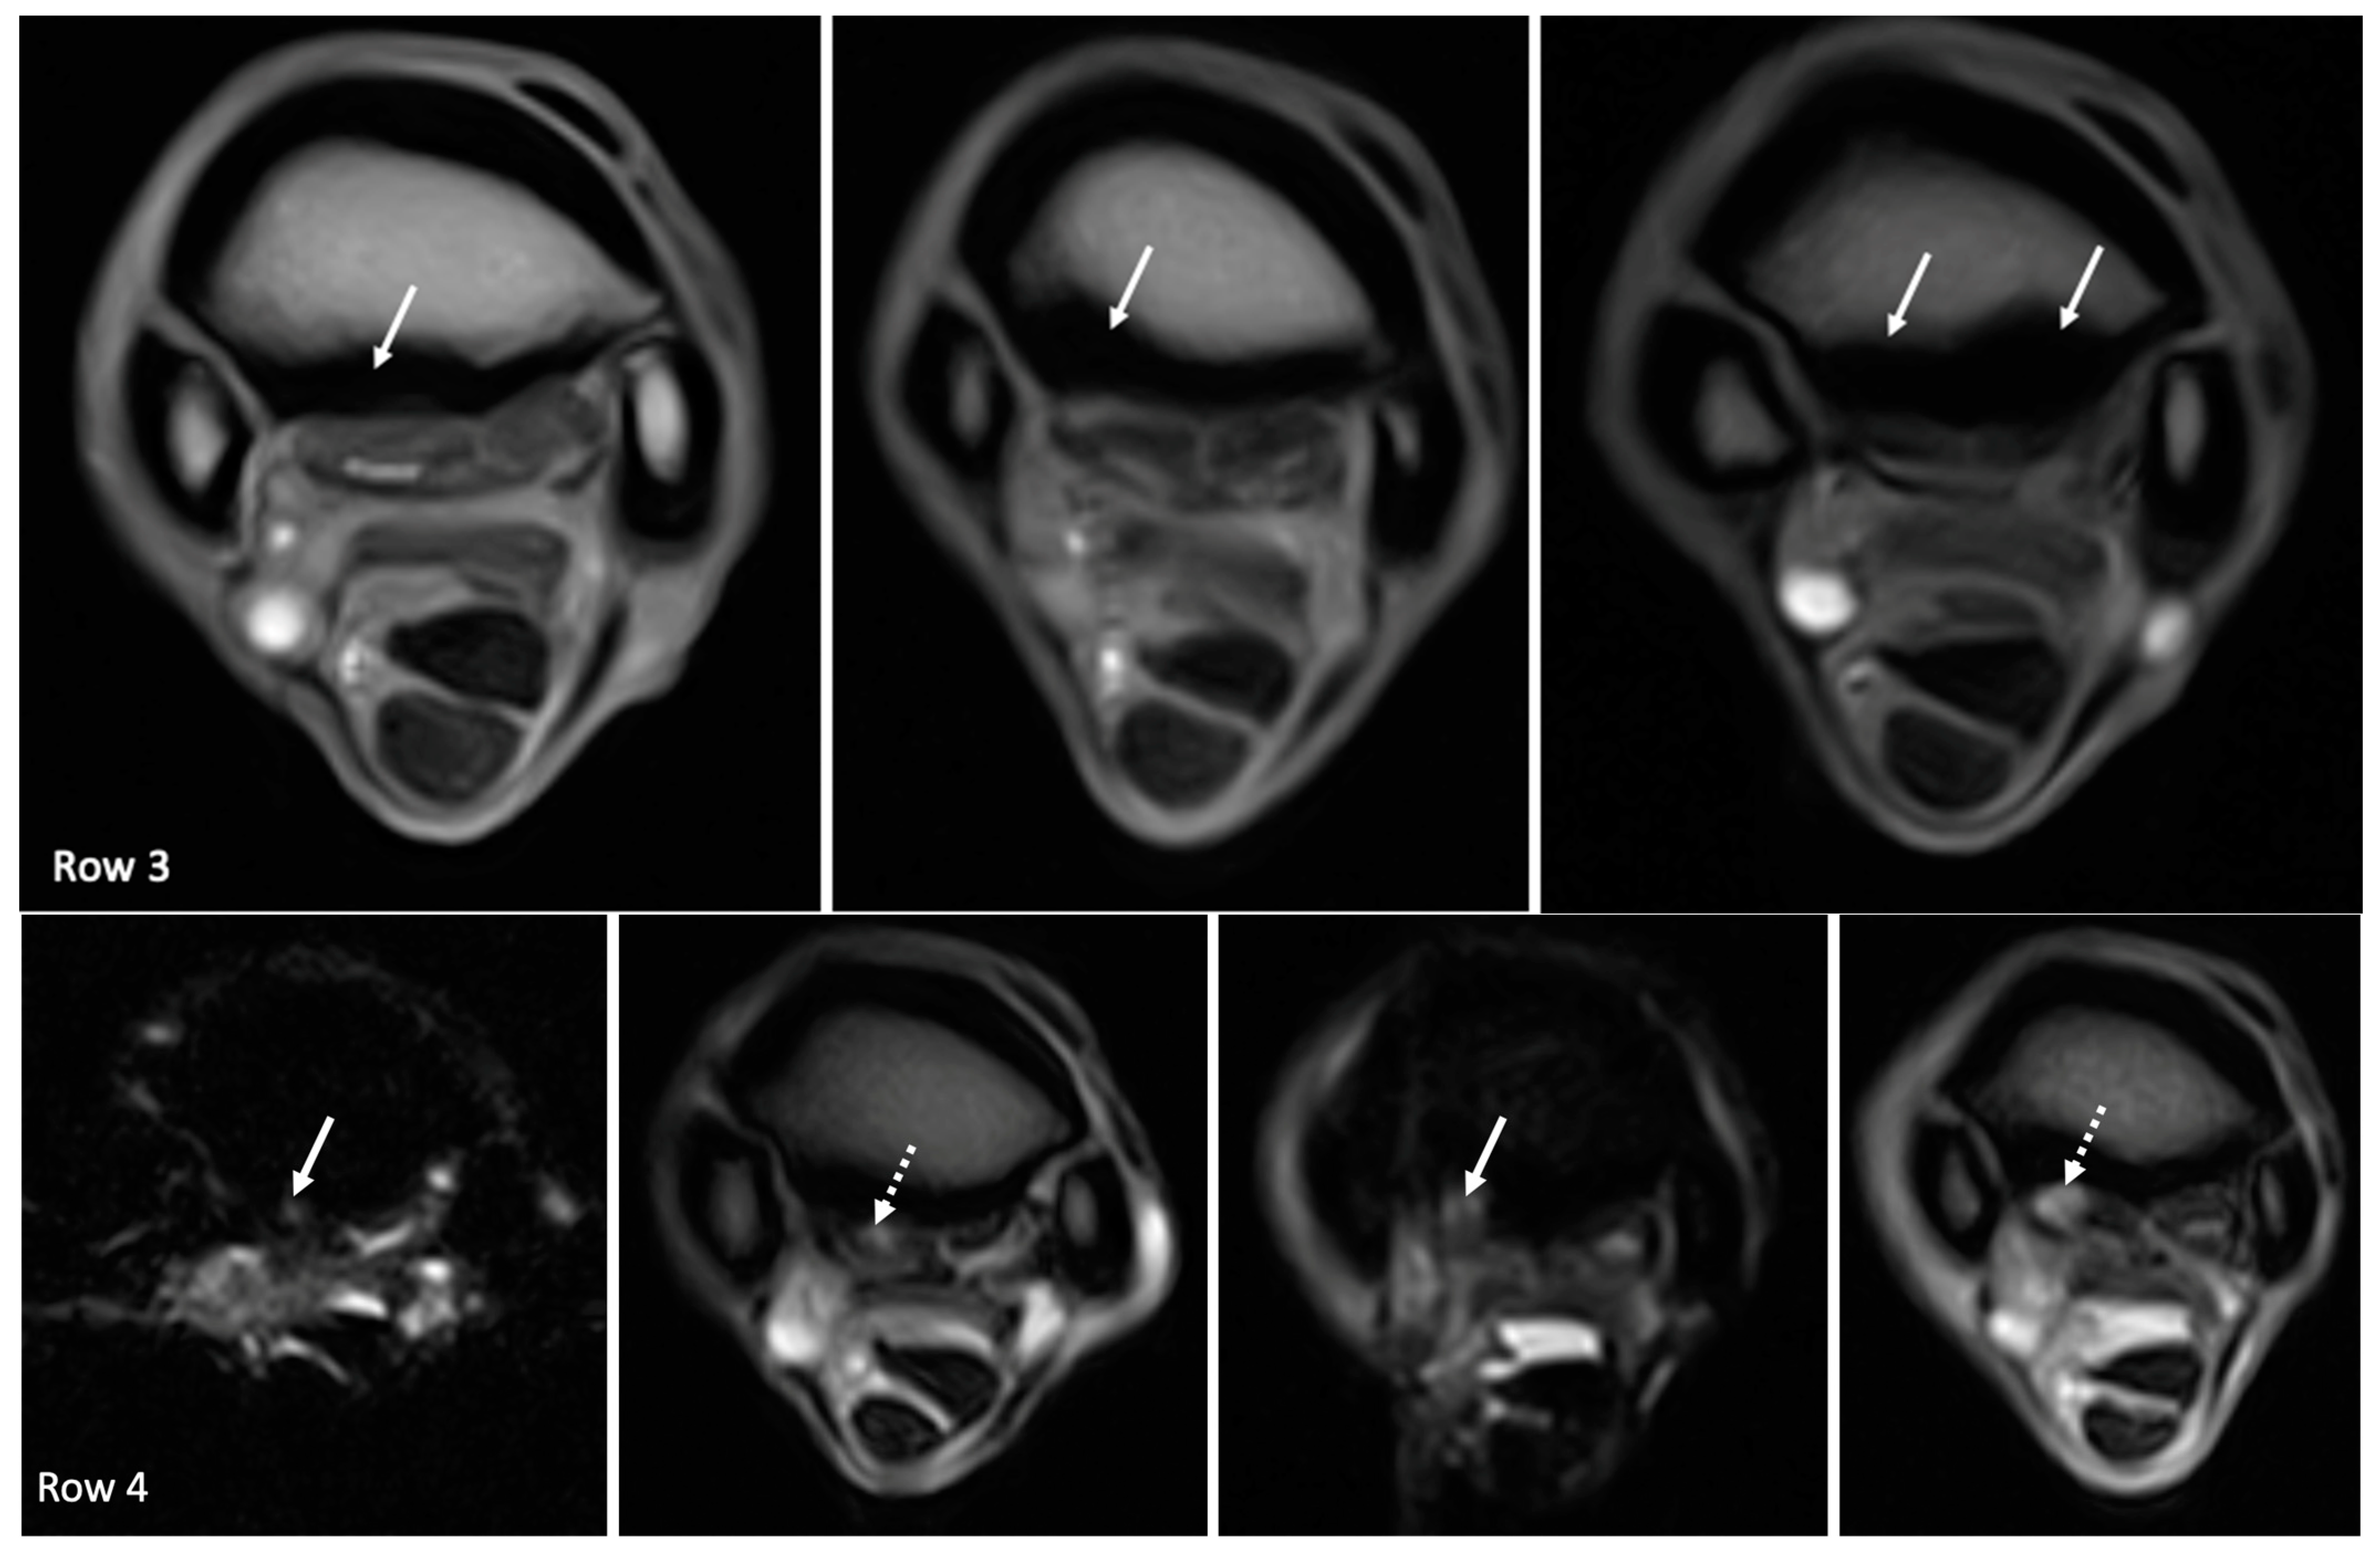

| Hyperintense signal on T1W GRE and T2*W GRE within the dorsal collagenous part of the PSL | 11/18 (61%) | 0/11 | 6/11 (55%) | 4/11 (36%) | 1/11 (9%) |

| Hyperintense STIR signal within the dorsal collagenous part of the PSL | 5/18 (28%) | 4/5 (80%) | - | 1/5 (20%) | - |

| Hyperintense signal on T1W GRE and T2*W GRE within the dorsal collagenous part of the PSL | Grade 0: 7 limbs Grade 1: 5 limbs Grade 2: 5 limbs Grade 3: 1 limb | Grade 0: 7 limbs Grade 1: 10 limbs Grade 2: 1 limbs Grade 3: 0 limbs |

| Hyperintense STIR signal within the dorsal collagenous part of the PSL | Grade 0: 13 limbs Grade 1: 1 limb Grade 2: 4 limbs Grade 3: 0 limb | Grade 0: 17 limbs Grade 1: 0 limbs Grade 2: 1 limbs Grade 3: 0 limbs |